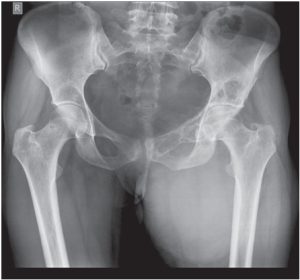

Conventional radiography of pelvis (Anterior posterior view) showed a large soft tissue mass in left medial thigh showing foci of calcification [Fig. 1]. Expansile lytic destruction of left hemi-pelvis was noted predominantly involving superior pubic ramus and acetabular roof. Possibility of “chondroid” tumour was based on radiographic findings. Chest radiograph of the patient was normal.

Imaging plays a pivotal role in diagnosis of hydatid cyst as imaging findings are classical while various serological tests often yield negative results [9]. Ultrasonographic findings of muscular hydatidosis are same as elsewhere with multi-septated cystic mass showing daughter cysts, floating membranes (water-lily sign), calcification and hydatid sand. Bony involvement of hydatid cyst is characterized by expansile lytic lesion with cortical thinning with computed tomography being a better modality than conventional radiography to characterize these findings. It does not show typical “spherical” lesion as pericyst formation does not take place, moreover bone being rigid, cyst usually enlarges in an irregular branching fashion along the path of least resistance [4] as in our case.